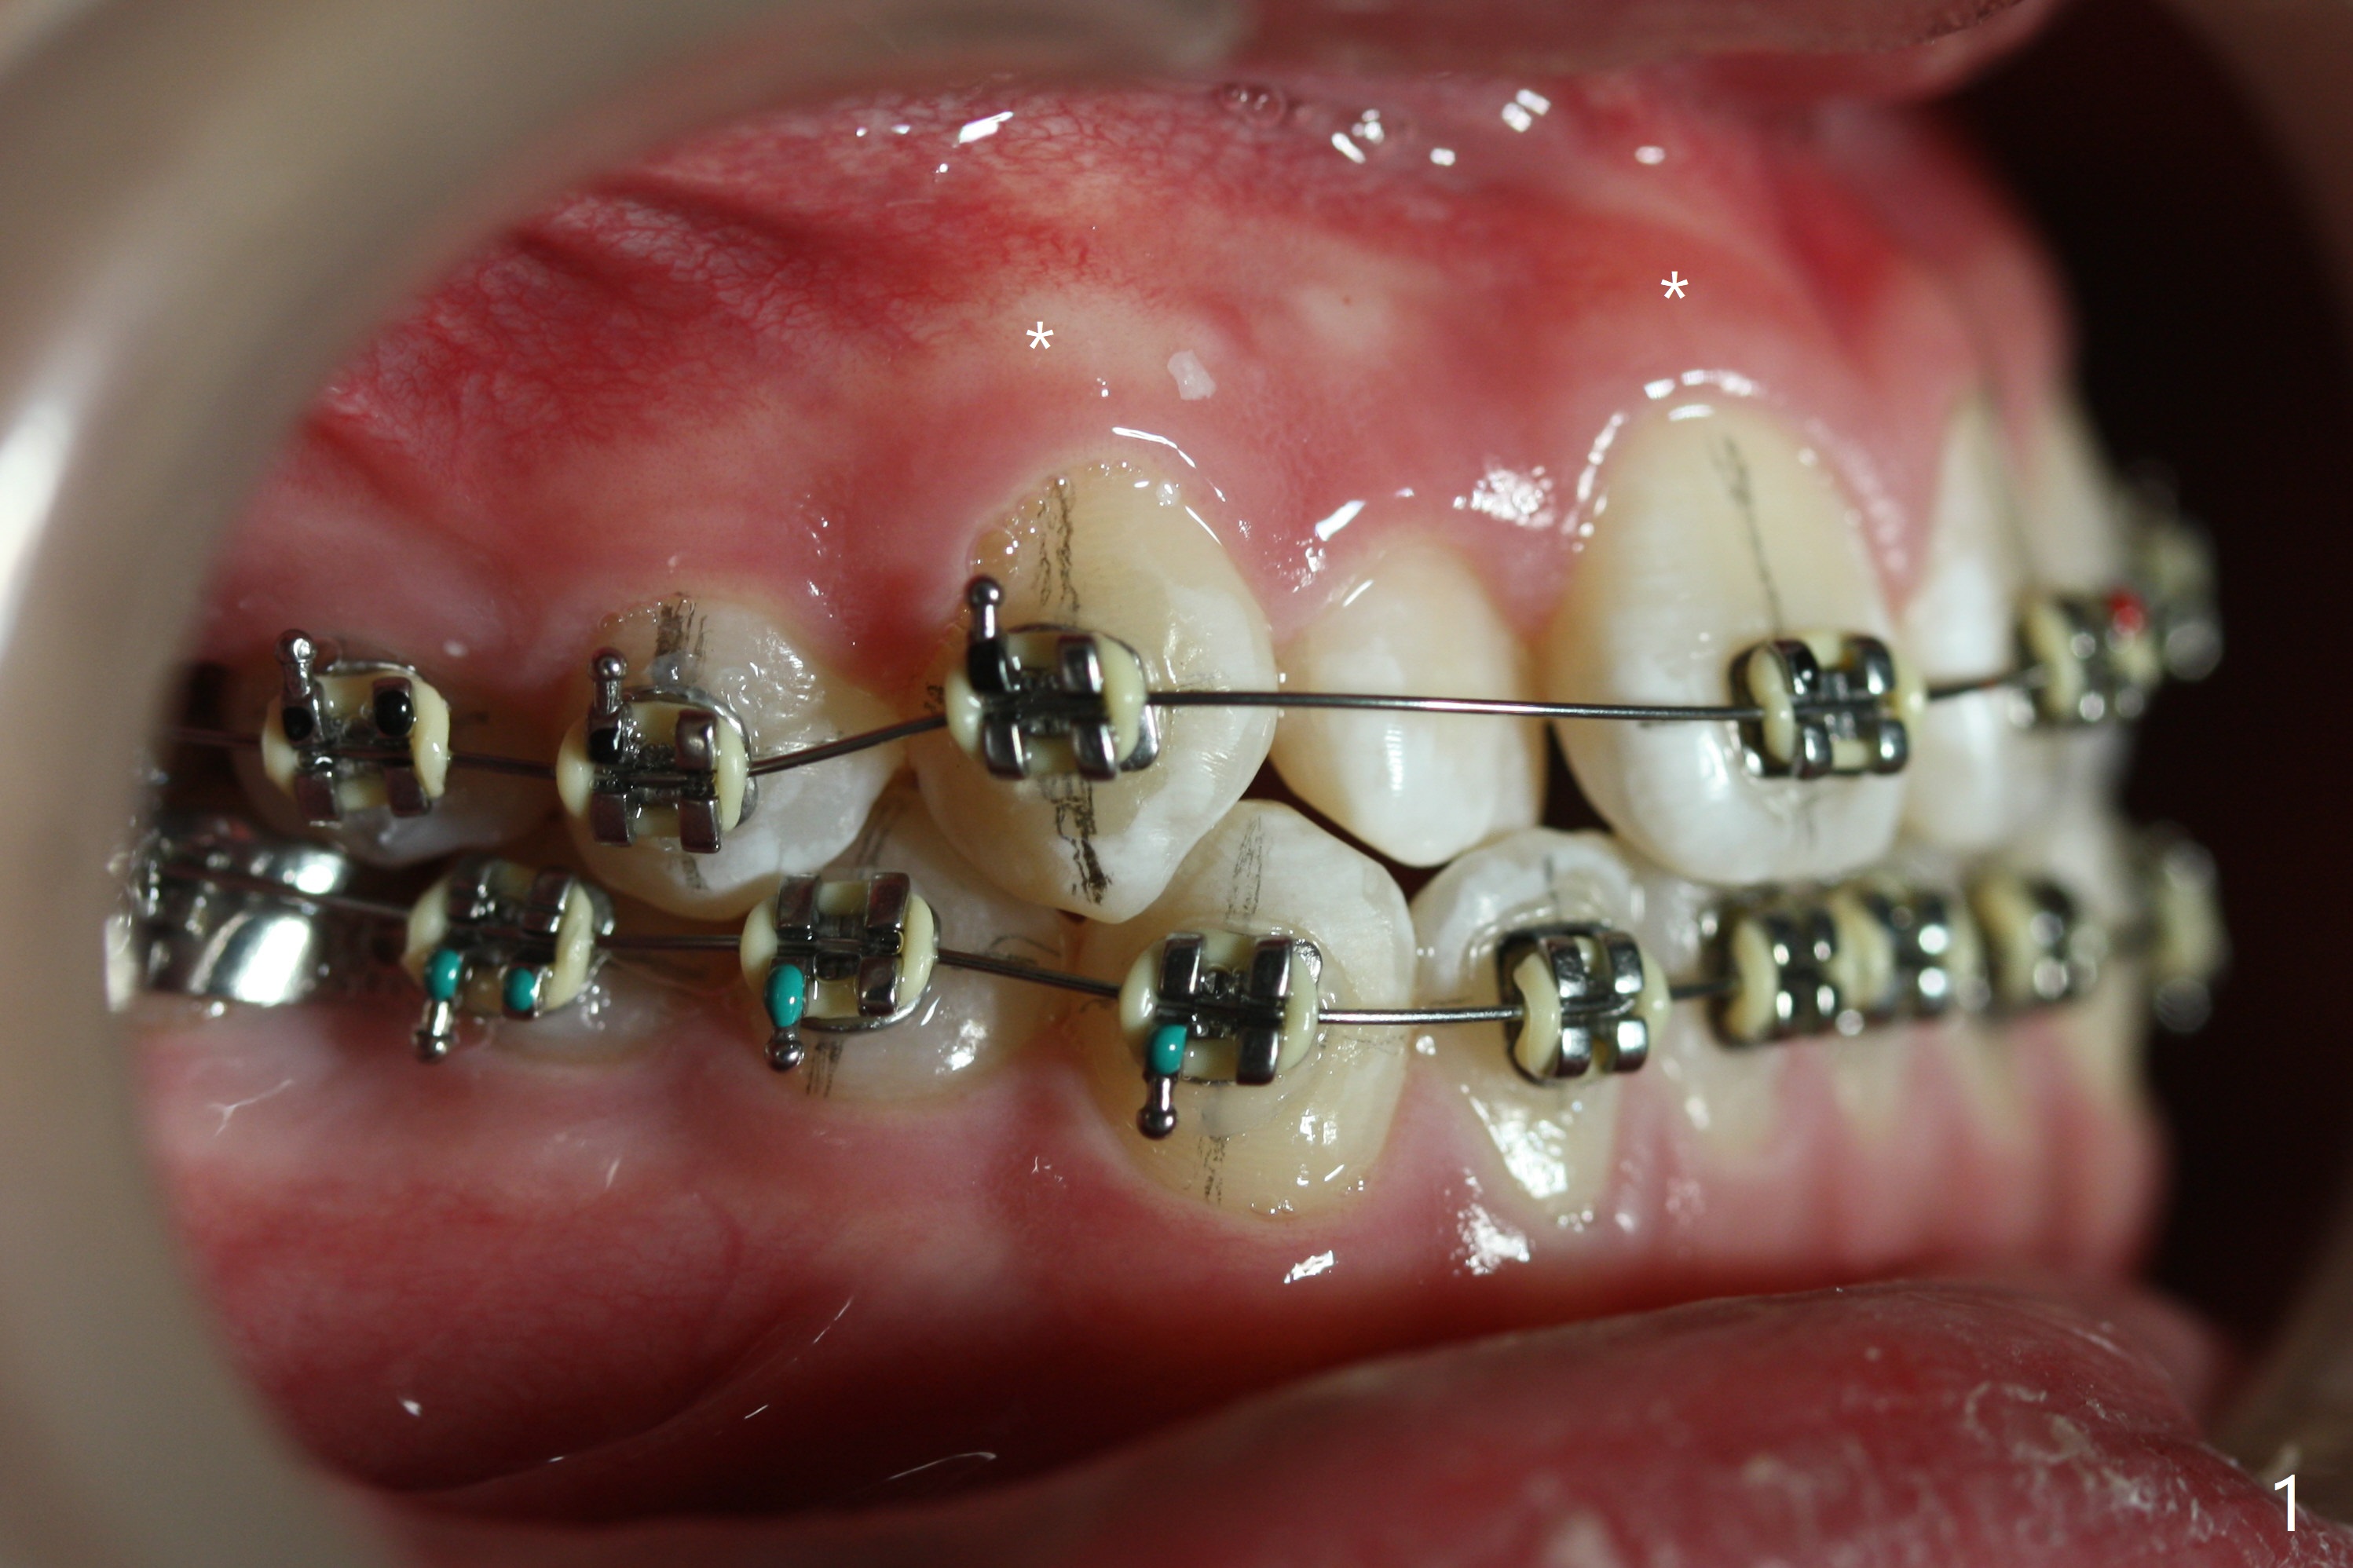

Cephalometric analysis shows Class III skeletal relationship. The roots of the upper anterior teeth (Fig.1,3 *) are prominent before treatment. In order to correct the cross bite of U2s (Fig.2,5), the upper arch needs expansion (Fig.4). Will the arch expansion cause buccal plate loss of the upper teeth? The upper dental midline matches the lower one by using the left open coil spring only (4 months 10 days post banding, Fig.6).